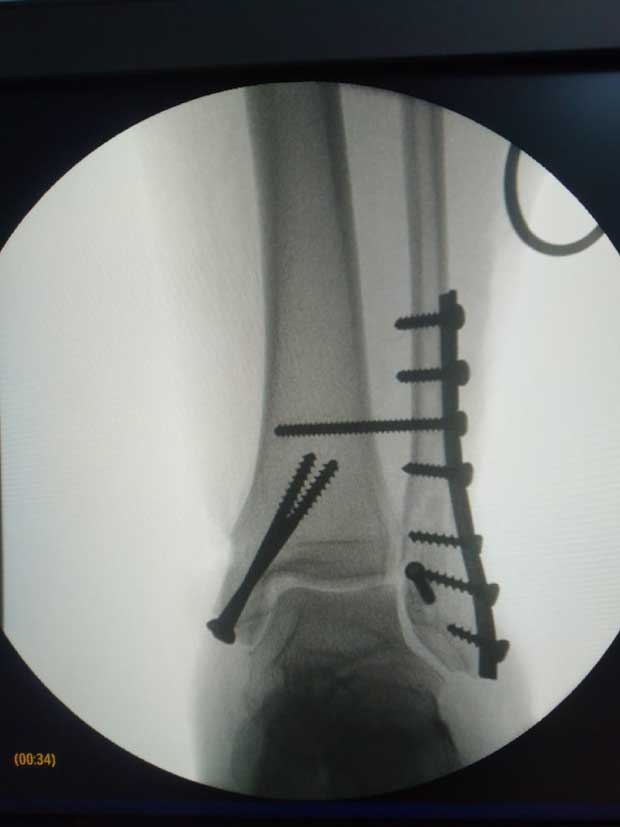

Caso No. 10 - Luxofractura de tobillo

Preoperación

Posoperación

Diagnóstico: Luxofractura de tobillo

Rx de perfil transoperatoria

Rx transoperatoria anteroposterior

Tratamiento: Cirugía: reducción abierta y fijación interna